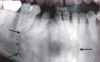

What is this radiographical finding?

Metastatic Carcinoma to Jaw Bones

C. Periapical image of a metastatic lesion of breast carcinoma; note the irregular widening of the periodontal membrane spaces and patchy sclerotic bone reaction, especially around the roots of the molars